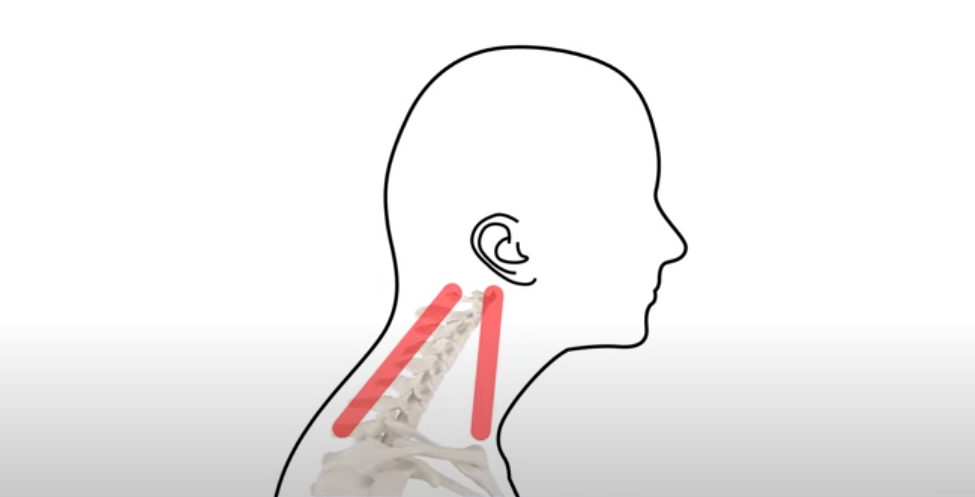

이 그림을 보시죠.

거북목이 지속되면 이 목 앞쪽 근육은 짧아지면서 뭉치고,

이 목 뒤쪽 근육은 앞으로 밀려 나간 머리를 붙잡느라 늘어나면서 긴장되고 아픕니다.

그래서 목 통증은 주로 뒷목 통증이 심하지만 진짜 치료해야 할 중요한 근육은 목 앞쪽 근육입니다. 그런데 대부분 목 통증을 치료할 때 통증이 심한 목 뒤쪽 근육이나 어깨, 승모근 쪽만 치료하는 경향이 있습니다. 그런 식으로 목 뒤쪽만 치료하면 정작 제일 중요한 목 앞쪽 근육의 문제가 남기 때문에 좋아져도 통증이 단기간이고, 근본적으로 좋아지기 어렵습니다.

목 앞쪽 근육 치료가 왜 중요하냐면 얼굴과 머리, 팔로 가는 수많은 신경과 혈관이 목 앞쪽 근육 사이를 통과하기 때문에, 목 앞쪽 근육이 뭉치고 단축되면 앞서 말씀 드린 온갖 증상들이 나타나는 원인이 됩니다. 그래서 목 앞쪽 근육 치료가 매우 중요한데, 한 가지 어려운 점은 목 앞쪽 근육 사이로 수많은 신경과 혈관이 지나가기 때문에 침, 약침, 봉침 치료가 고난도의 치료라는 겁니다. 그래서 고도로 숙련된 시술자가 매우 주의해서 해야 합니다.